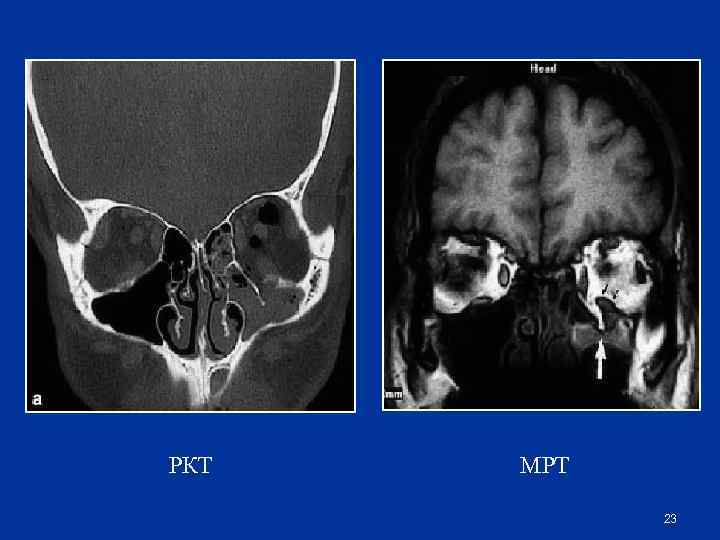

РКТ МРТ 23